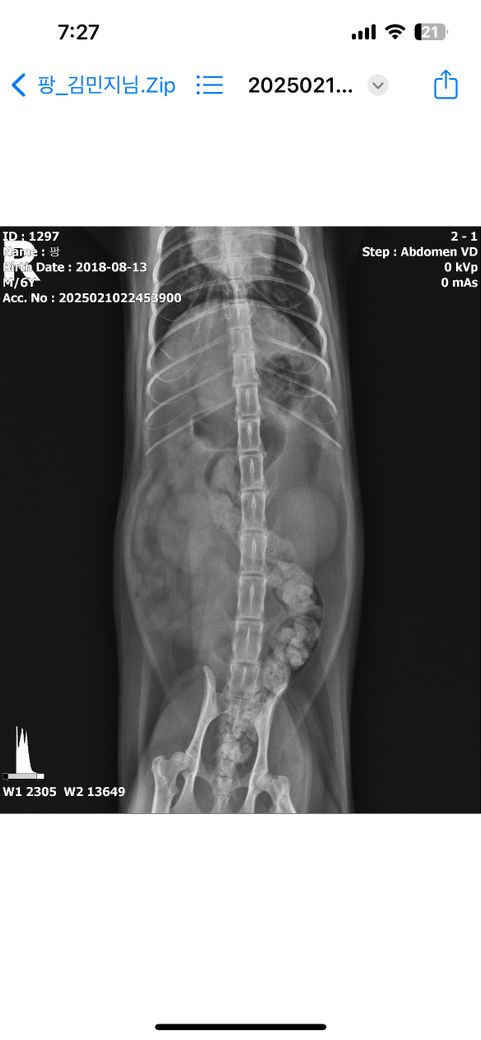

동물 병원에서 구토억제제만 처방받았고 이 엑스레이 보고서 가스찬거 말곤 별다른 증상 없다 하셨습니다. 다른선생님들도 같은 생각이신지 궁금하여 올려봅니다

거대 결장을 동반한 대장의 확장 수준이라 거대 결장과 관련한 기저 질환에 대한 평가가 필요한 수준이니 https://diamed.tistory.com/m/145 주치의와 상담 후 정밀 검사를 받으시는걸 추천합니다.